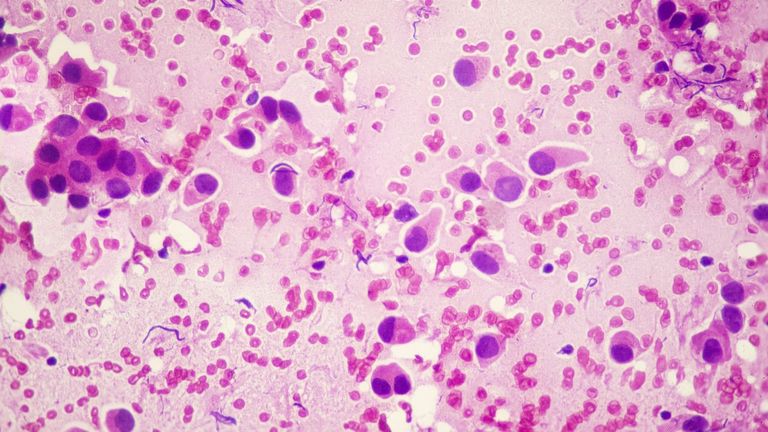

Investigadores del CNIO avanzan en la identificación de las lesiones que se convertirán en tumores, lo que podrá ayudar a evitar un sobretratamiento que ocurre en el 20 % de los casos